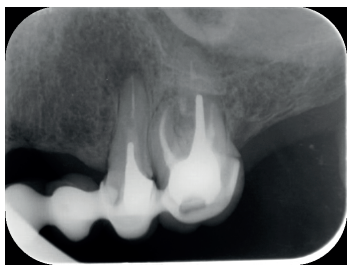

El paciente aporta como estudio radiológico una ortopantomografía (OPG), (Figura 1). Se realizaron radiografías periapicales (Figuras 2 y 3), así como exploración clínica incluyendo la valoración periodontal de los dientes afectados, sin observar profundidades de sondaje aumentadas que pudieran indicar la existencia de lesiones endoperiodontales.